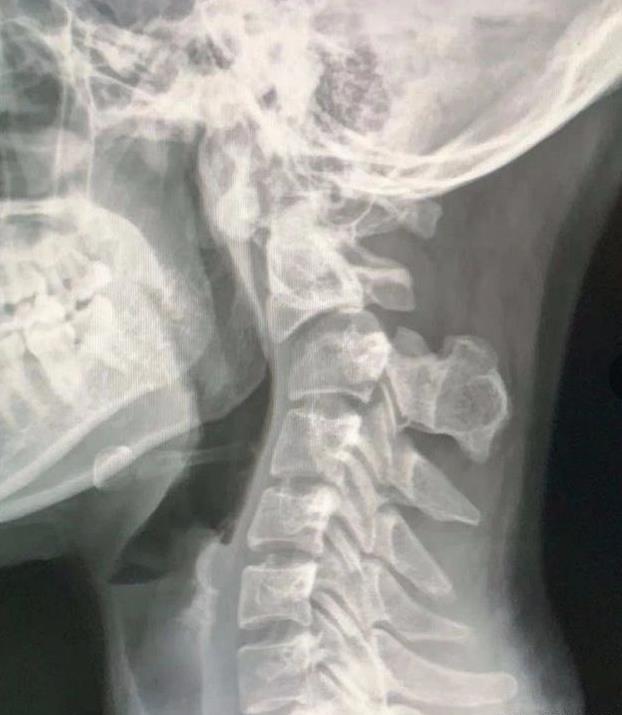

“会”是因为 , 据泰国警方的调查和法医鉴定 , 查雅达死于颈部错位压力下导致的神经元爆裂 。

也就是说 , 查雅达的去世确实与那场按摩有着不可分割的联系 。

据悉 , 11月6号那天 , 查雅达因为长时间的颈椎酸痛决定去做一场按摩 , 试图缓解肩颈部位的不适 。

但是这场按摩的效果显然没有她想的那么好 , 按摩结束两天后 , 查雅达的后颈出现针扎一般的疼痛情况 。

其实现在想想 , 或许在那时查雅达的颈椎就已经发生错位 , 开始压迫神经元了 , 只是还不算非常严重而已 。

一周之后 , 查雅达的手臂开始出现麻痹症状 , 但这时她依旧没有警惕起来 , 甚至还再次选择了同一家店进行按摩 。

第二次按摩后 , 查雅达的疼痛加剧 , 还出现了身体僵硬的情况 , 最后她甚至没办法从床上坐起来 。

值得一提的是 , 之所以会发生这样的情况 , 或许与店里的按摩师在第二次按摩中多次扭动查雅达的颈部有关 。

这次按摩之后 , 查雅达的情况急转直下 , 她的右手无法举起 , 下半身甚至直接瘫痪 。